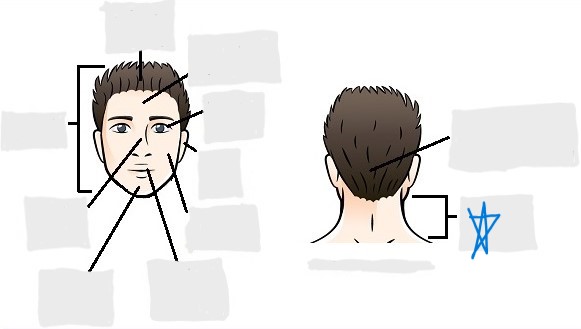

axial

cephalic

occipital

frontal

otic

orbital

nasal

oral

mental

cervical